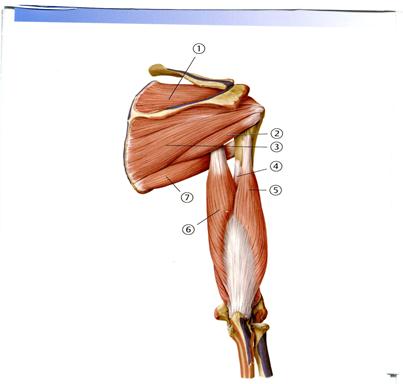

49. Төменде көрсетілген суреттегі белгіленген № 3 бұлшықетті атаңыз.

А. Алдыңғы тісшеленген

В. Екібасты бұлшықеттің ұзын басы

С. Екібасты бұлшықеттің қысқа басы

++D. Жауырынасты

Е. Үлкен жұмыр

52. Төменде көрсетілген суреттегі белгіленген № 1 бұлшықетті атаңыз.

А. Кіші жұмыр

В. Қылқанасты

+С. Қылқанүсті

D. Үш басты бұлшықеттің ұзын басы

Е. Үлкен жұмыр